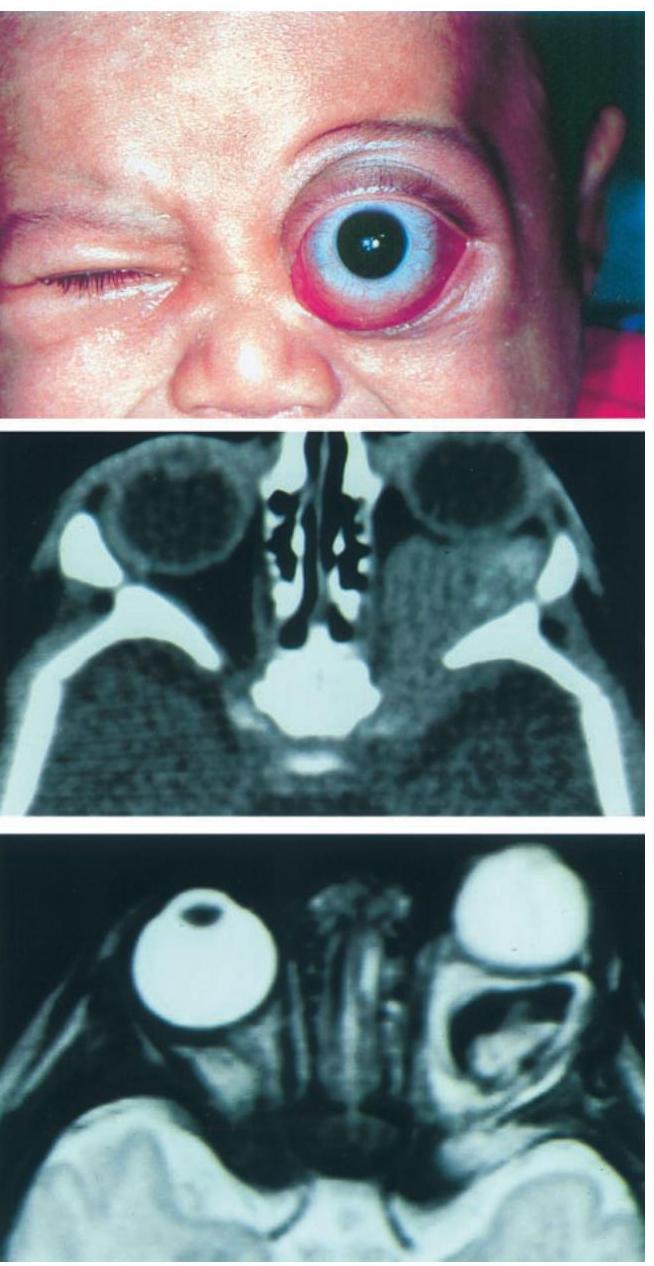

Orbital Lymphatic Malformation (Lymphangioma)

Orbital lymphangioma | PPTX